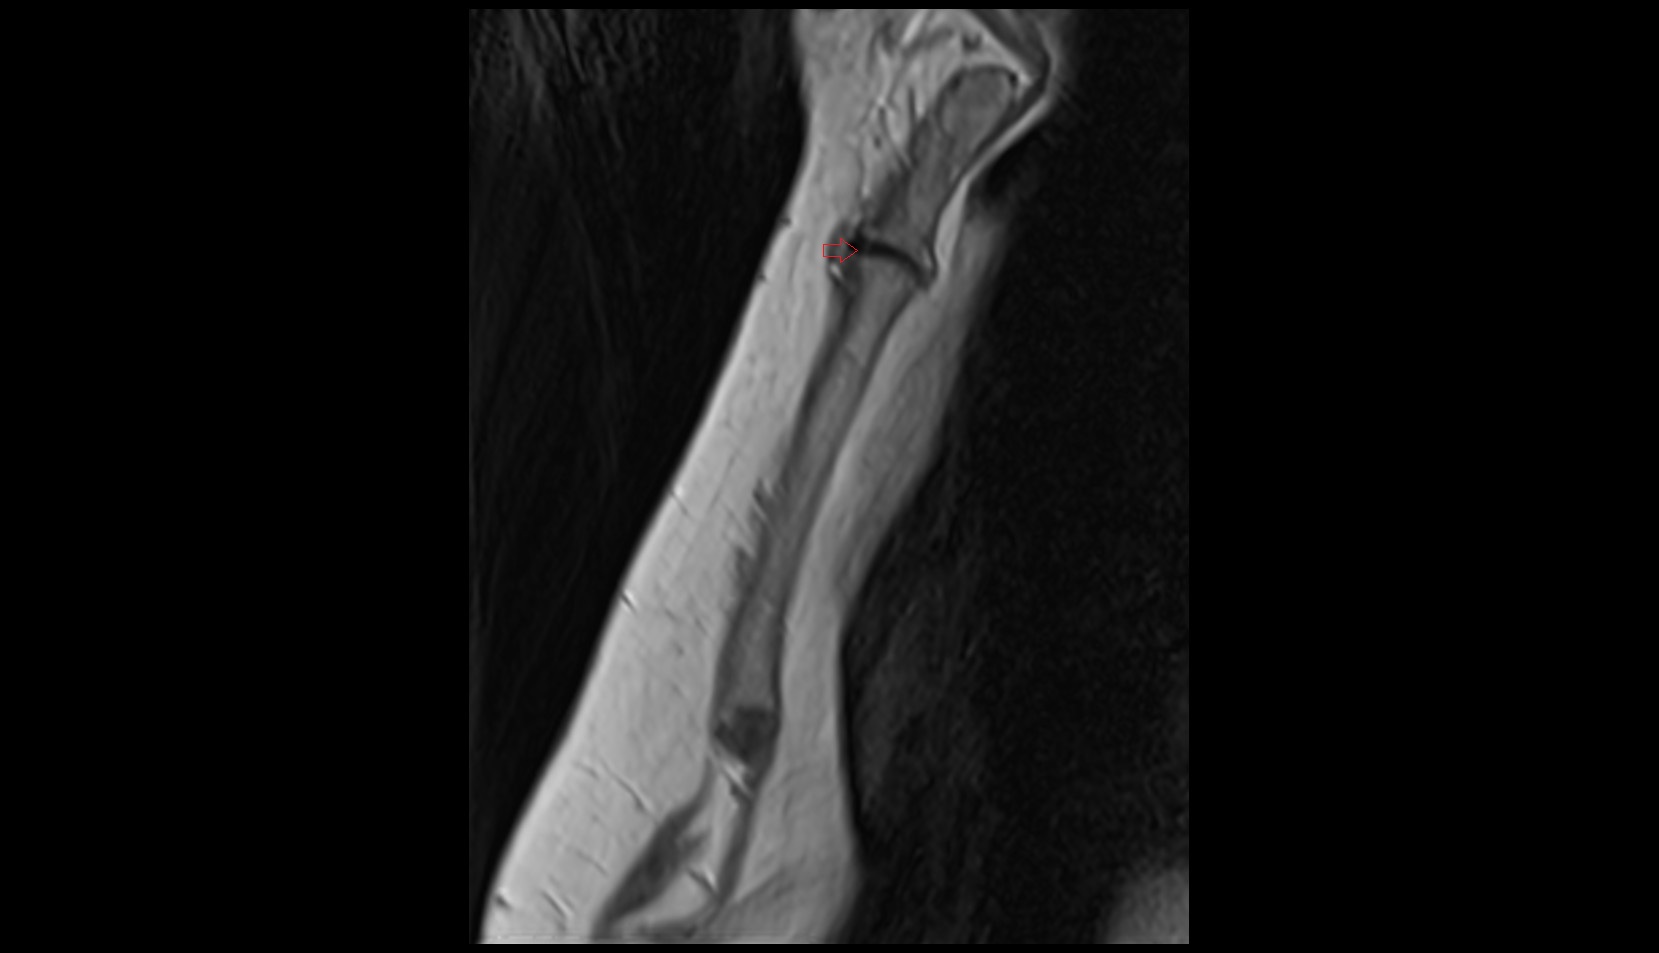

- Tibia

- Fibula